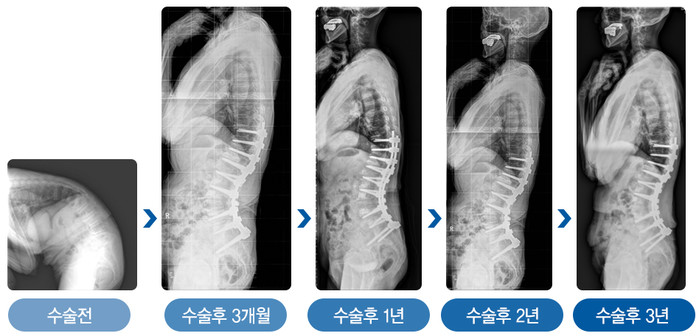

| ▲그림2. 심한 노인성 후만변형으로 수술을 받은 78세 환자 (여)는 수술 3년 후에도 허리곡선이 잘 유지되고 있다. |